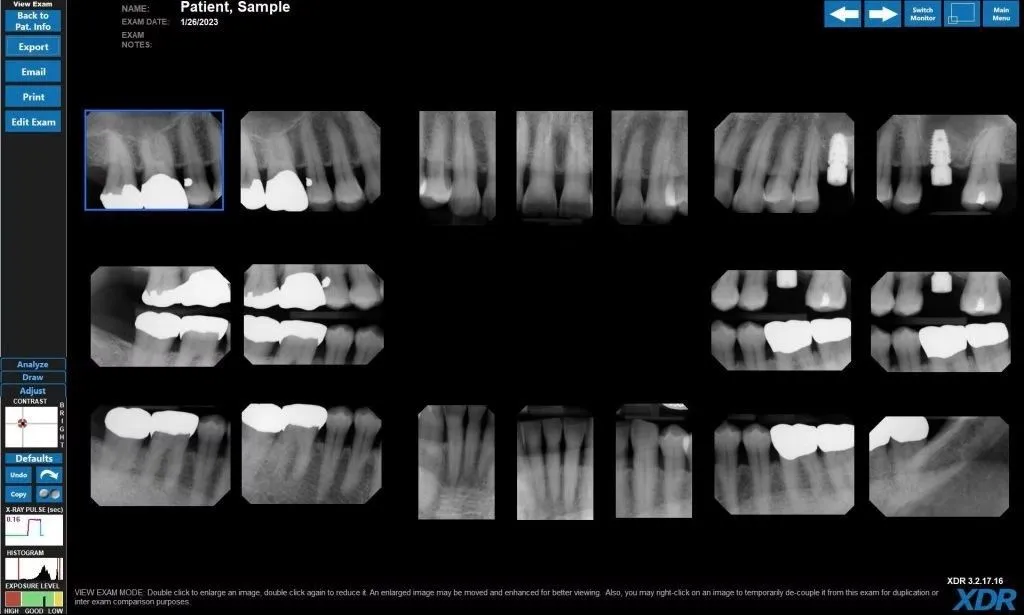

At our practice, your safety is just as important as your oral health. That’s why we use advanced digital X-ray technology that delivers high-resolution images while significantly reducing your exposure to radiation.

Digital radiography allows us to detect dental conditions that may not be visible during a routine clinical exam—such as bone loss, infections, root fractures, and periodontal defects. With enhanced clarity and precision, we can diagnose problems earlier and provide more effective treatment plans.

Our low-dose digital X-ray system emits up to 80–90% less radiation than traditional film-based X-rays. The actual radiation dose is extremely low—comparable to what you receive from a few hours of natural background exposure in your daily environment.